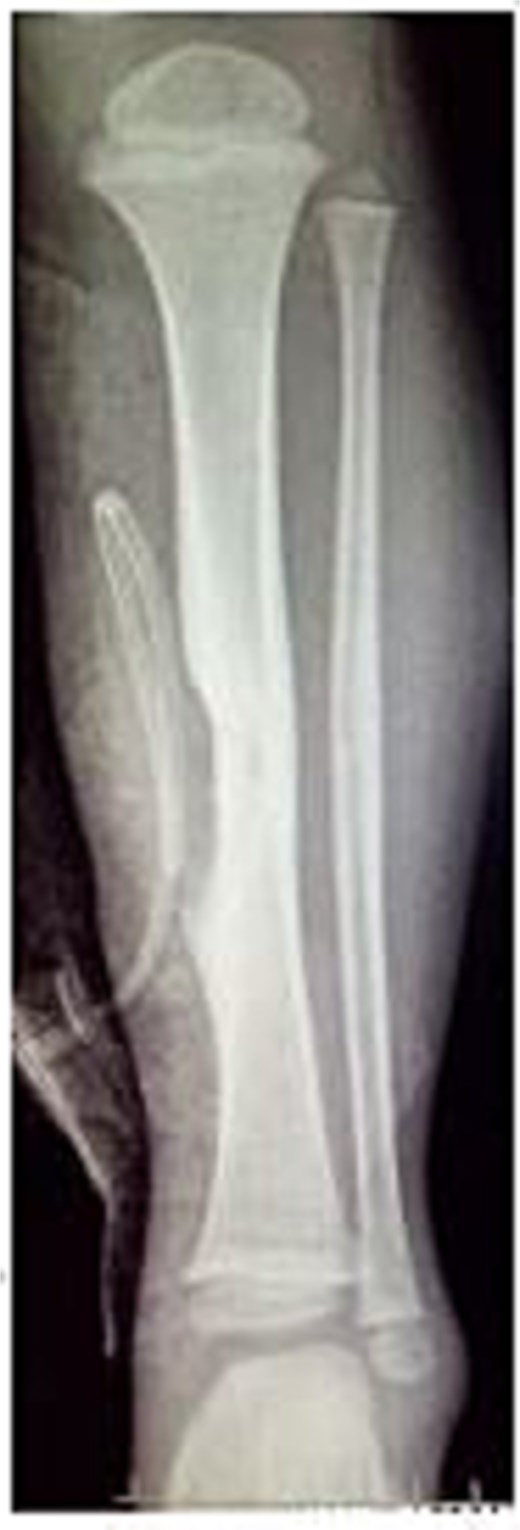

A 4-year-old boy presented with swelling on the medial aspect of his left leg. Three months prior, the patient had sustained a left tibial shaft fracture, initially treated conservatively. The swelling developed gradually with localized tenderness. On examination, the swelling was firm and tender to palpation, with intact overlying skin (Fig. 1). Radiography revealed erosion of the tibia (Fig. 2). Given the patient's fracture history, the initial differential included osteomyelitis, and empirical antibiotics were started. The vascular surgery team suspected a pseudoaneurysm and recommended further evaluation. Doppler ultrasound confirmed a pseudoaneurysm, revealing an abnormal vascular structure with turbulent blood flow. To delineate the vascular anatomy and identify the pseudoaneurysm's origin, magnetic resonance angiography (MRA) was ordered. It demonstrated the pseudoaneurysm arising from an unnamed posterior tibial artery branch, likely injured during initial trauma. The aneurysmal sac was located near the fracture site, eroding the underlying tibial bone (Fig. 3). The pseudoaneurysm's size warranted surgical intervention. The patient underwent excision of the aneurysmal sac and vessel wall repair (Fig. 4). Under general anesthesia, the aneurysmal sac was dissected out (Fig. 5), and the posterior tibial artery wall was repaired with lateral sutures. Hemostasis was achieved, and the wound was closed in layers. The patient had an uneventful postoperative recovery.

Clinical picture of the patient's left leg showing swelling on the medial aspect.